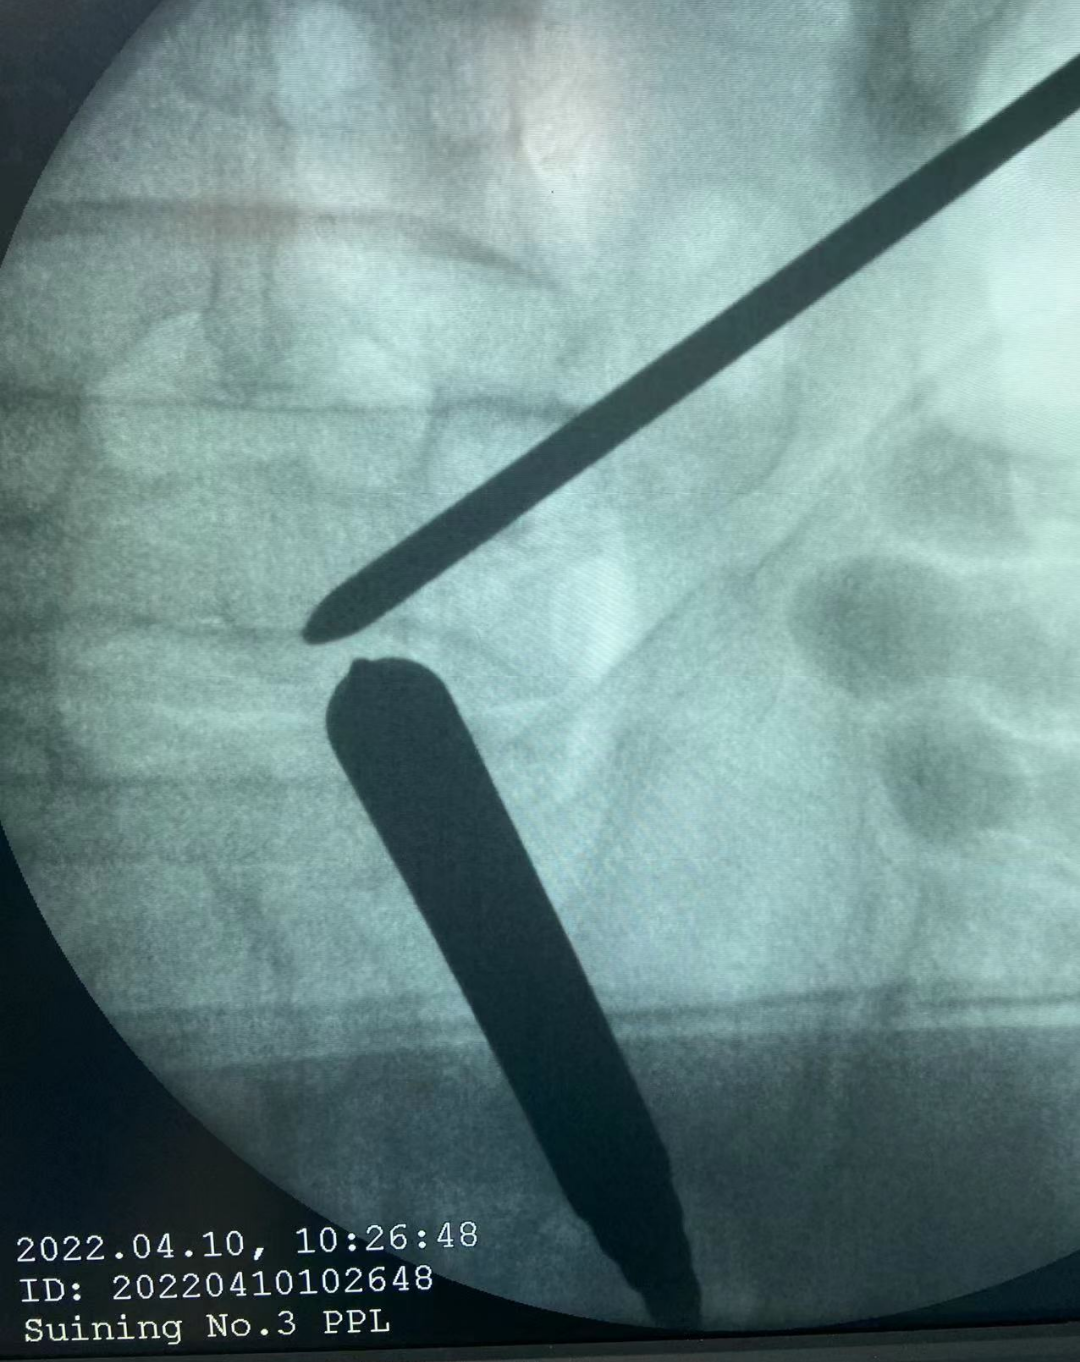

科室设备先进,拥有西门子C臂X光机、床旁X光机、storz关节镜、Arthroscope System关节镜、骨科多功能手术床、脊柱手术器械、关节置换器械、骨科牵引床、各种物理作业康复设备等,进口西门子、高清晰移动C臂X光机能满足骨科各种有创治疗需要,使创伤最小各种复位更精确、内固定更安全可靠,同时科室备有进口的storz关节镜,常年开展膝关节镜治疗膝、肩关节内疾病,且有各种康复治疗设备,充分满足骨科患者治疗的需求。